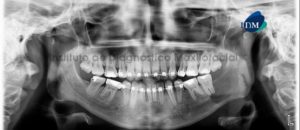

Paciente masculino, 17 años de edad, es referido al Instituto de Diagnóstico Maxilofacial (IDM) para evaluación tomográfica de premolar retenido. En la radiografía panorámica (Figura